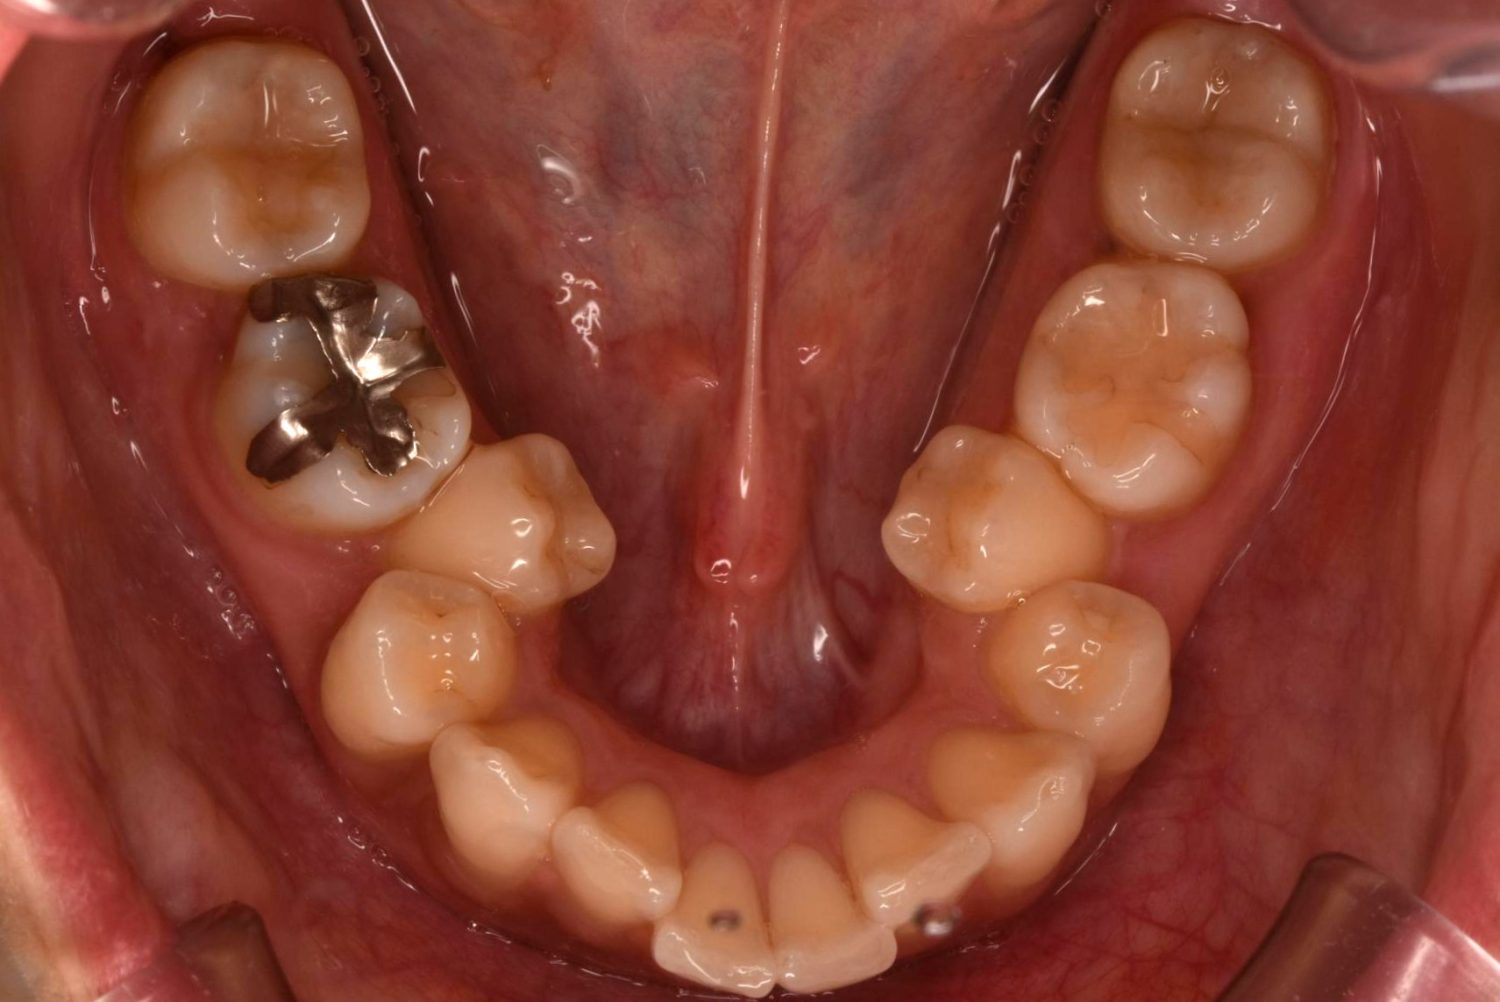

| 主訴 | 20代女性の患者さん。右上の八重歯が突出しており、前歯の見た目にコンプレックスを抱いていた。下顎の左右第2小臼歯(5番)が舌側に大きく傾斜しており、食事の際に、食べかすが詰まりやすく日常的に不快感を覚えていた。噛み合わせの改善と、見た目のバランスを整えたいという希望があり、矯正治療を行うことになった。また、目立ちにくい方法で治療を進めたいという意向から、マウスピース型装置の矯正 “インビザライン”を希望。 |

| 治療内容 | 下顎の左右第2小臼歯(5番)は舌側に大きく傾斜しており、矯正治療における歯の移動効率や全体の歯列バランスを考慮し、便宜抜歯を行った。また、上顎の左右第1小臼歯(4番)についてもスペース確保の目的で抜歯を実施し、全顎的な歯列の配列を円滑に進められるよう計画。矯正装置は、患者さんのなるべく目立ちにくい治療を行いたいという強い希望とライフスタイルに合わせて、マウスピース型矯正装置「インビザライン」(※1)を採用。抜歯が必要となる矯正治療は、診断・治療の難易度が高い方法である。当院ではCTやセファログラムなどの先進的な設備を完備し、多角的な診査診断と豊富な臨床経験をもつ理事長による治療を行うことで、このような難症例にも対応可能。 また、当院は矯正治療だけでなく、むし歯治療やクリーニングなどの一般歯科・予防治療も一貫して管理する包括的な審美治療を行う総合クリニック。治療中にむし歯などの問題が見つかっても、すぐに対応できるため、患者さんの通院の負担をできる限り抑えたスムーズな対応が可能。矯正専門医院ではできない包括的なサポート体制こそが、シャングリラデンタル横浜歯科矯正歯科で矯正治療を受けるメリットである。 矯正治療中は定期検診で経過の確認とクリーニングを行い、必要に応じて治療計画の見直しやマウスピース型装置の追加を行った。患者さんの高い装着遵守率も相まって、歯列は順調に整い、機能的にも審美的にも良好な結果をえることができた。 (※1)未承認医薬品等であるため医薬品副作用被害救済制度の対象とはならない可能性があります。 |